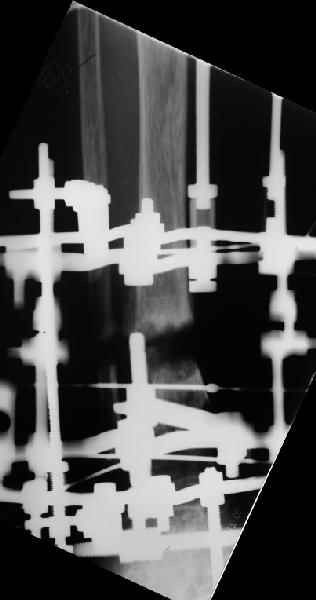

Аппарат - чтобы плавно исправить ось. В приложении - снимки на момент окончания коррекции в аппарате, фото с операции, и послеоперационная рентгенограмма.

Диаметр гвоздика 10,5 мм. Пришлось укорачивать до 23 см - уж очень миниатюрная дама, отверстия насверлил под 45 градусов, под 5 мм винты. По оси удалось сблизить до этого положения. Заперли гвоздь пока статически с планом через 2 месяца верхний винт убрать. Но это ей придется уже в Ташкенте сделать. Что скажете? Спасибо.

In attachment - x-rays at the end of alignment, the surgery, and result. The nail was cut to 23 cm. Four 45 degree holes were pre-drilled at the distal nail tip. The nail was locked statically